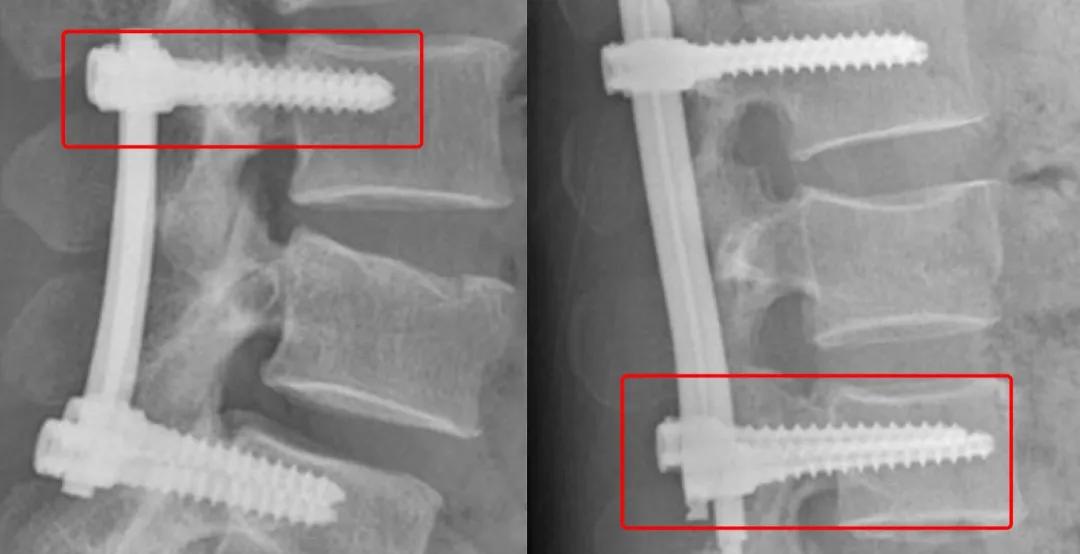

当事医生刘爱华告诉丁香园,专业医生是可以看出微创钉与普通钉的区别的:「我是从 X 光片发现的不对。微创钉在片子上是空心的,而普通钉在片子上则是实心的。」

骨科医生王南(化名)也告诉丁香园:「片子上的螺钉是空心还是实心,可以作为患者使用的普通螺钉还是微创螺钉的参考鉴别,微创用的椎弓根螺钉一般为空心的,而开放用的椎弓根螺钉(包括普通螺钉、万向螺钉和长尾型螺钉)都是实心的,不过,有时候透视时两个螺钉重叠,从片子上可能就不易区别了。」

两种不同螺钉,左为实心,右为空心

此外,通过术后 X 线上棒的结构也可大致推测是经皮微创植入还是开放植入。经皮微创植入的棒,一般会有一端是尖的,而如果是开放植入的棒,那么两头都是一致的。

但从这张片子,加用的横连,从我的角度推测是开放植入的,一般微创植入不会用到横连。患者可能把开放用的长尾型椎弓根螺钉与微创经皮椎弓根螺钉混淆了。临床有时候根据开放手术需求会用到长尾型椎弓根螺钉和万向螺钉,以便于植入固定棒。

理论上微创手术,用的椎弓根螺钉不应该会与普通的椎弓根螺钉混淆,因为设计不同,普通的椎弓根螺钉不可能微创植入的。」